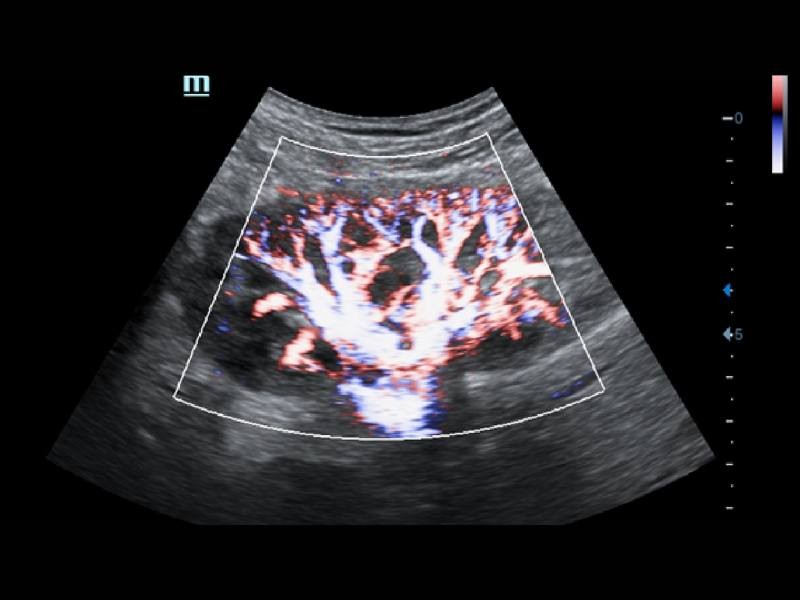

O Smart Track proporciona uma otimização rápida e inteligente das imagens vasculares com apenas um toque. Ele pode otimizar o espectro de cor, energia e PW por meio de rastreamento automático e reduz as etapas demoradas. Portanto, o fluxo de trabalho do exame vascular é simplificado por meio de uma visão ideal.